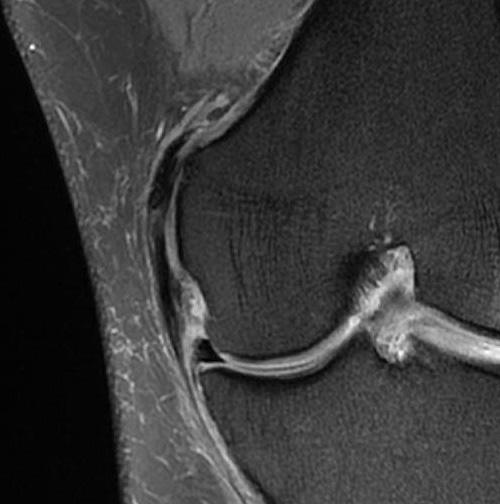

К сожалению, обызвествления плохо видны на МРТ мягких тканей и их сложнее подозревать, особенно в суставных зонах. Примером может служить болезнь Пеллигрини-Штиды (Pellegrini-Stieda). На МРТ коленного сустава можно заметить признаки сопутствующего синовита и иногда утолщение медиальной коллатеральной связки и энтезофиты.

Чаще всего изменения при МРТ колена рассматриваются как симптомы артроза, особенно если в анамнезе отсутствовали травмы. Кальцификация может локализоваться вдоль медиального мыщелка в мягких тканях, что делает её визуализацию на МРТ коленного сустава невозможной. В то же время на стандартных рентгенографиях в прямой проекции данная патология хорошо отчетливо видна.

МРТ коленного сустава. Корональная Т2-взвешенная МРТ с подавлением сигнала от жира. Болезнь Пеллигрини-Штиды.